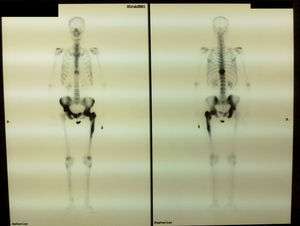

Con la sospecha de enfermedad de Paget se solicitó una gammagrafía ósea con Tc-99 (fig. 2), en la que se apreció un aumento de captación en la vértebra D 10, tercera articulación interfalángica proximal izquierda, pelvis y fémur izquierdo. Se solicitó radiología simple de las regiones captantes, destacando la afectación de la tercera falange de la mano izquierda, siendo el resto de la imagen radiográfica normal (fig. 3).

Las manifestaciones clínicas son silentes, no obstante puede ser un hallazgo casual al realizar una radiología posteroanterior de las manos, indicada por otro motivo. La presentación clínica de la afectación de los huesos de la mano suele ser la misma que en otras localizaciones, a saber: asintomática, deformidad, dolor y fractura.

La radiología ósea evidencia el patrón clásico de la enfermedad ósea de Paget, a saber, aumento de tamaño del hueso, la falta de diferenciación córtico-medular, imágenes líticas y esclerosis. La afectación de los huesos de la mano en la enfermedad ósea de Paget acontece en enfermedades poliostóticas, siendo más raros los casos monostóticos. No se describen osteosarcomas en esta localización.